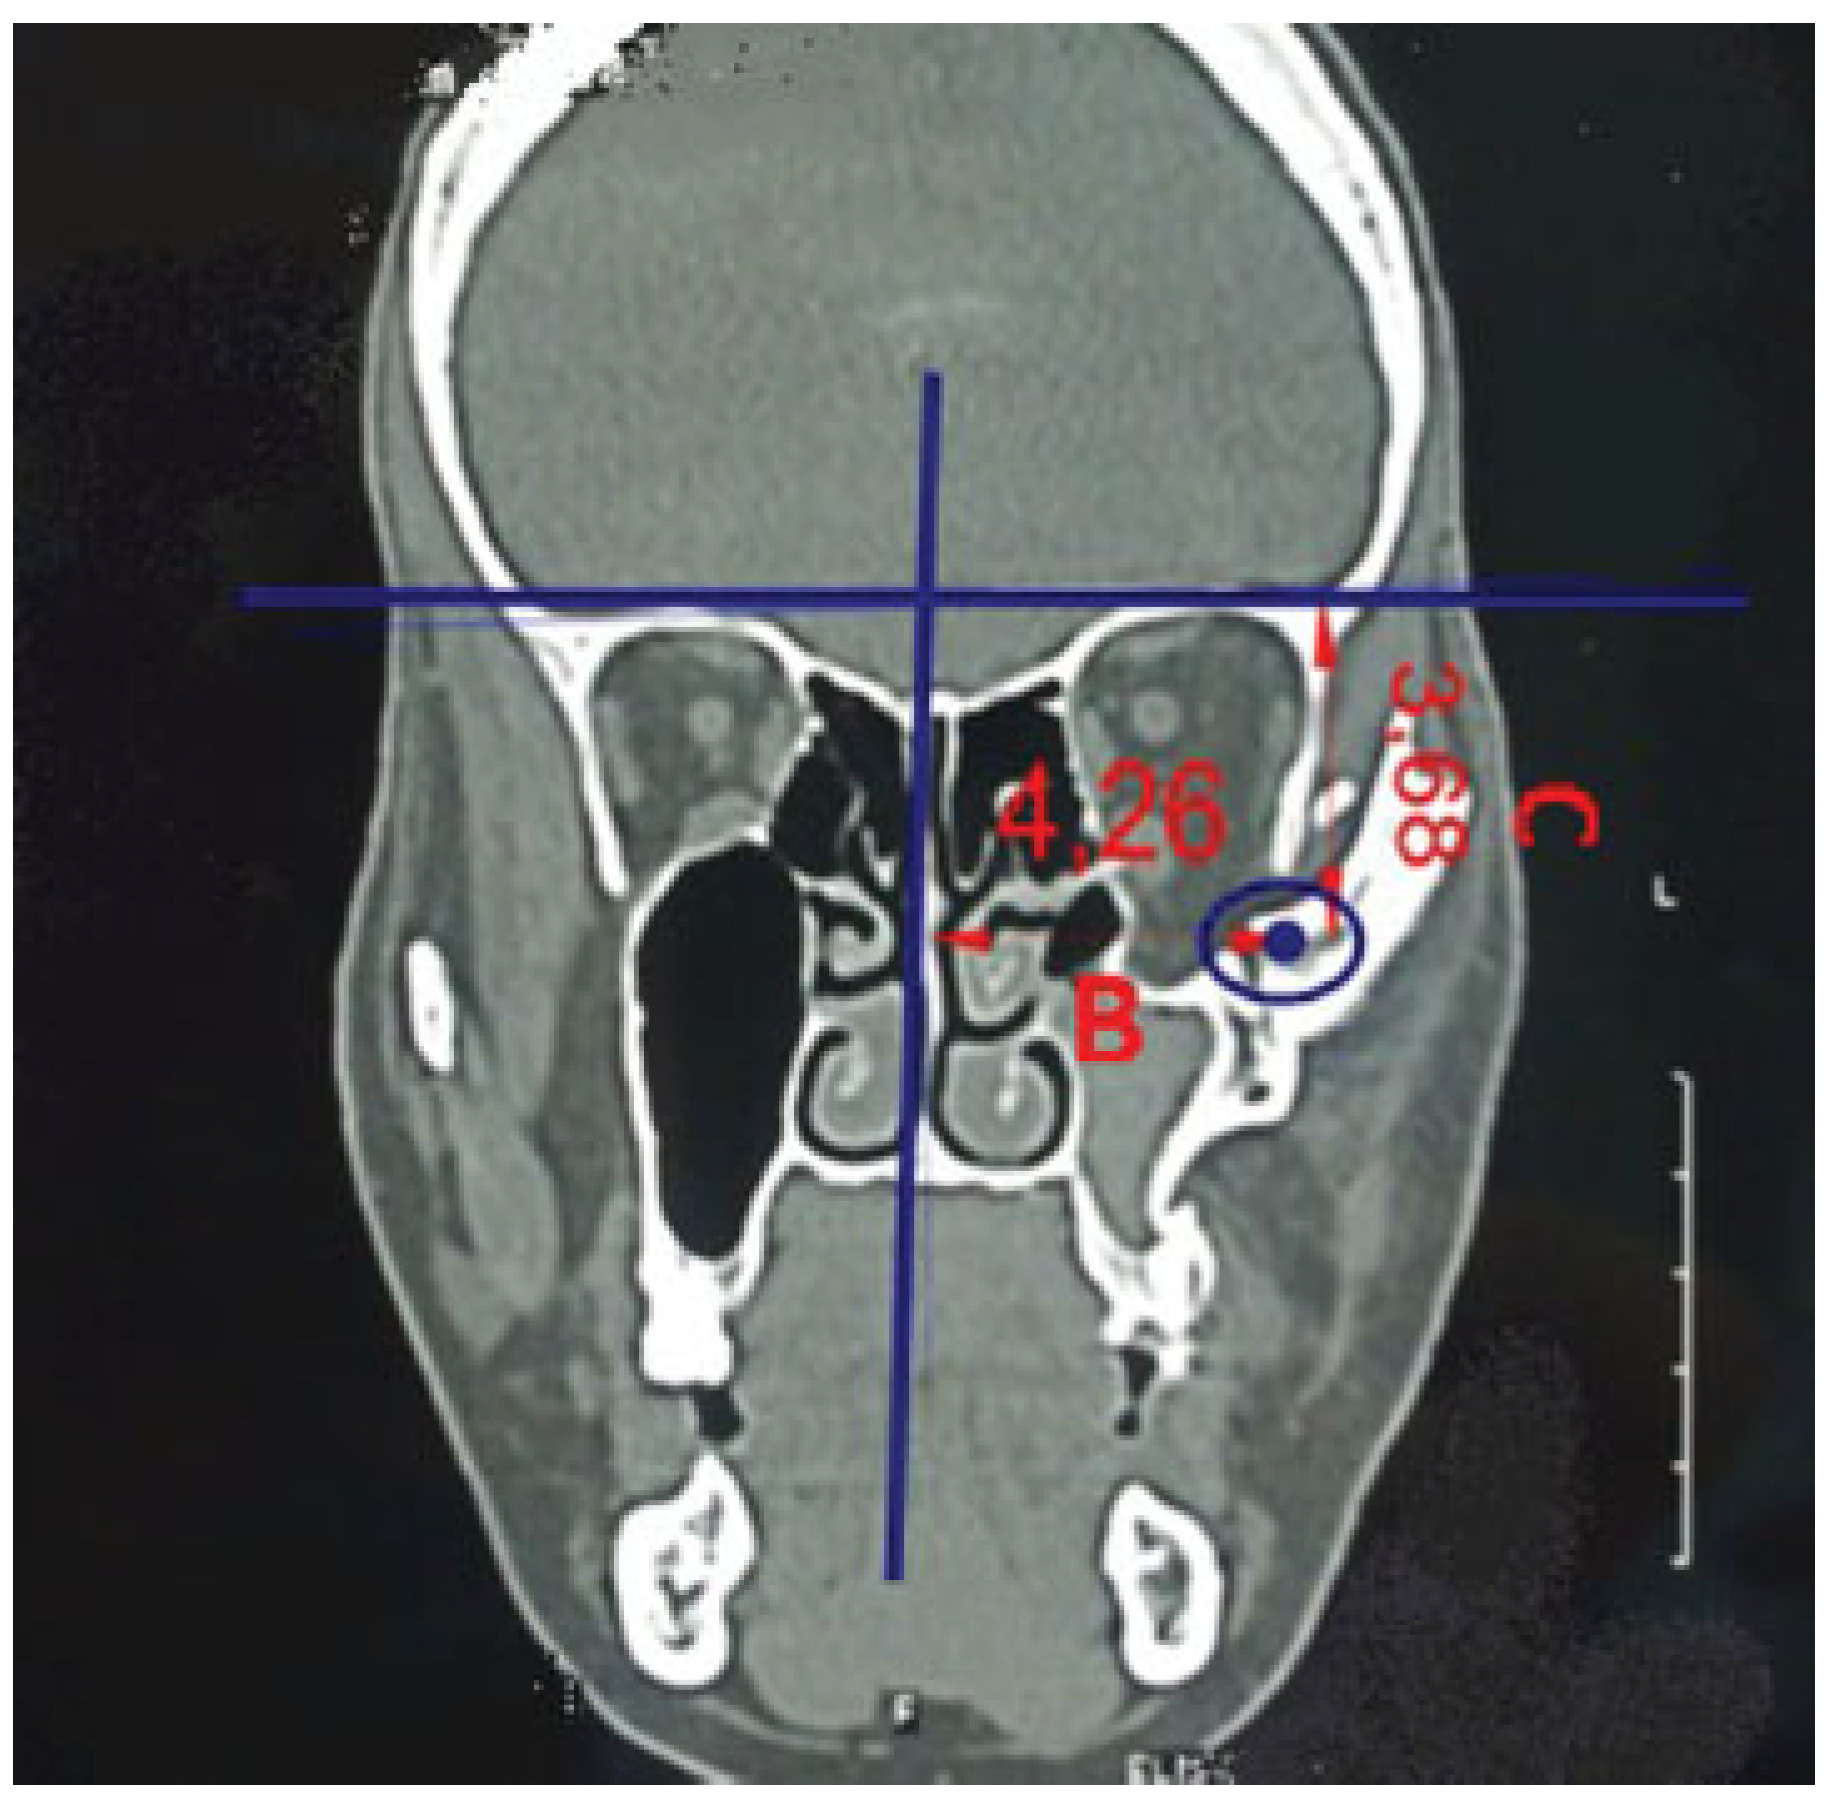

• Vertical change of inferior orbital rim (vertical step): Measure distance between two parallel lines drawn over inferior orbital rim on both sides (distance D; measurements in mm; modification from Kim et al[7]).

• Angle of displacement of zygoma: Angle between two parallel lines drawn over lateral surface of zygoma is estimated to assess medial and lateral displacement of zygoma (angle E; modification from Thiagarajan et al;[2] Figure 3).

Figure 3. Radiological assessment of zygomatic position in 3D view. Distance D—vertical change of inferior orbital rim. Vertical step: distance between two parallel lines drawn over inferior orbital rim on both sides (measurements in mm). Angle E—Angle of displacement of zygoma. Angle between two parallel lines drawn over lateral surface of zygoma is estimated to assess medial and lateral displacement of zygoma.